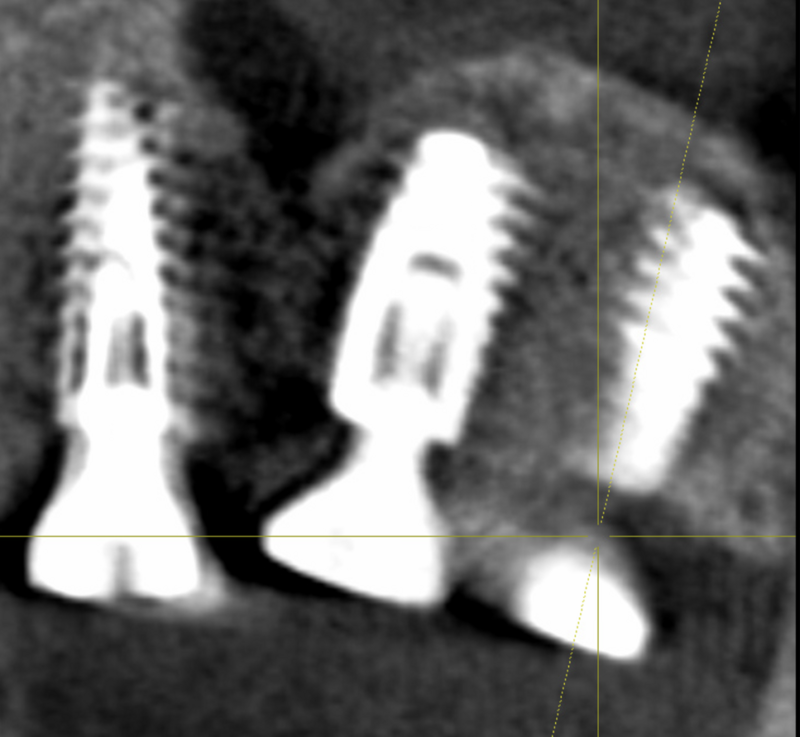

GREFFE OSSEUSE SOUS SINUSIENNE ET RECONSTRUCTION DE CRETE EN EPAISSEUR

AVANT APRES ELEVATION OSSEUSE SOUS-SINUSIENNE